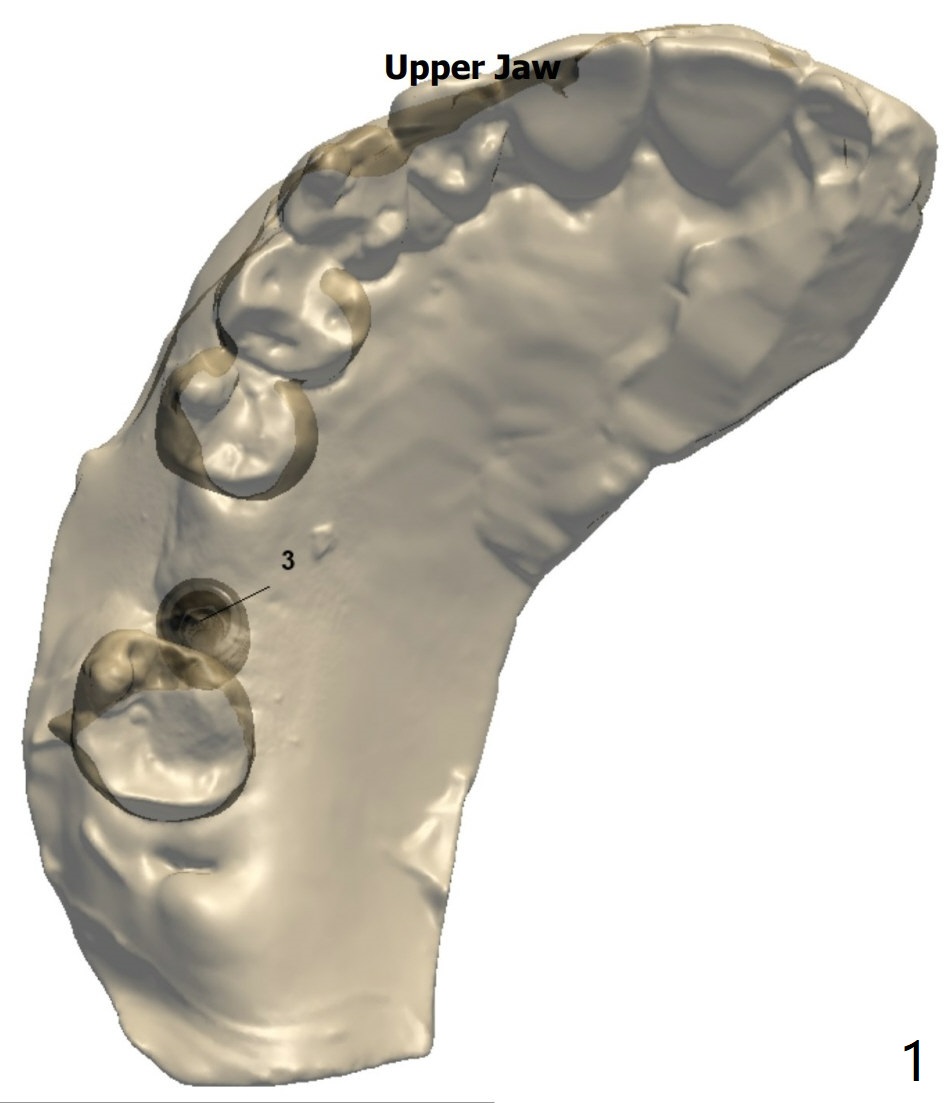

Low Density, Murky Bone Boundary

A -year-old man.  PRFx2